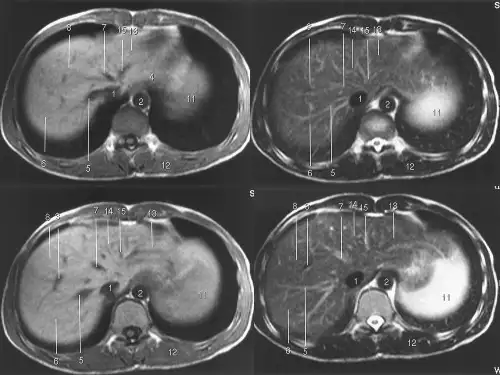

Magnetic Resonance Imaging (MRI) of the Abdomen